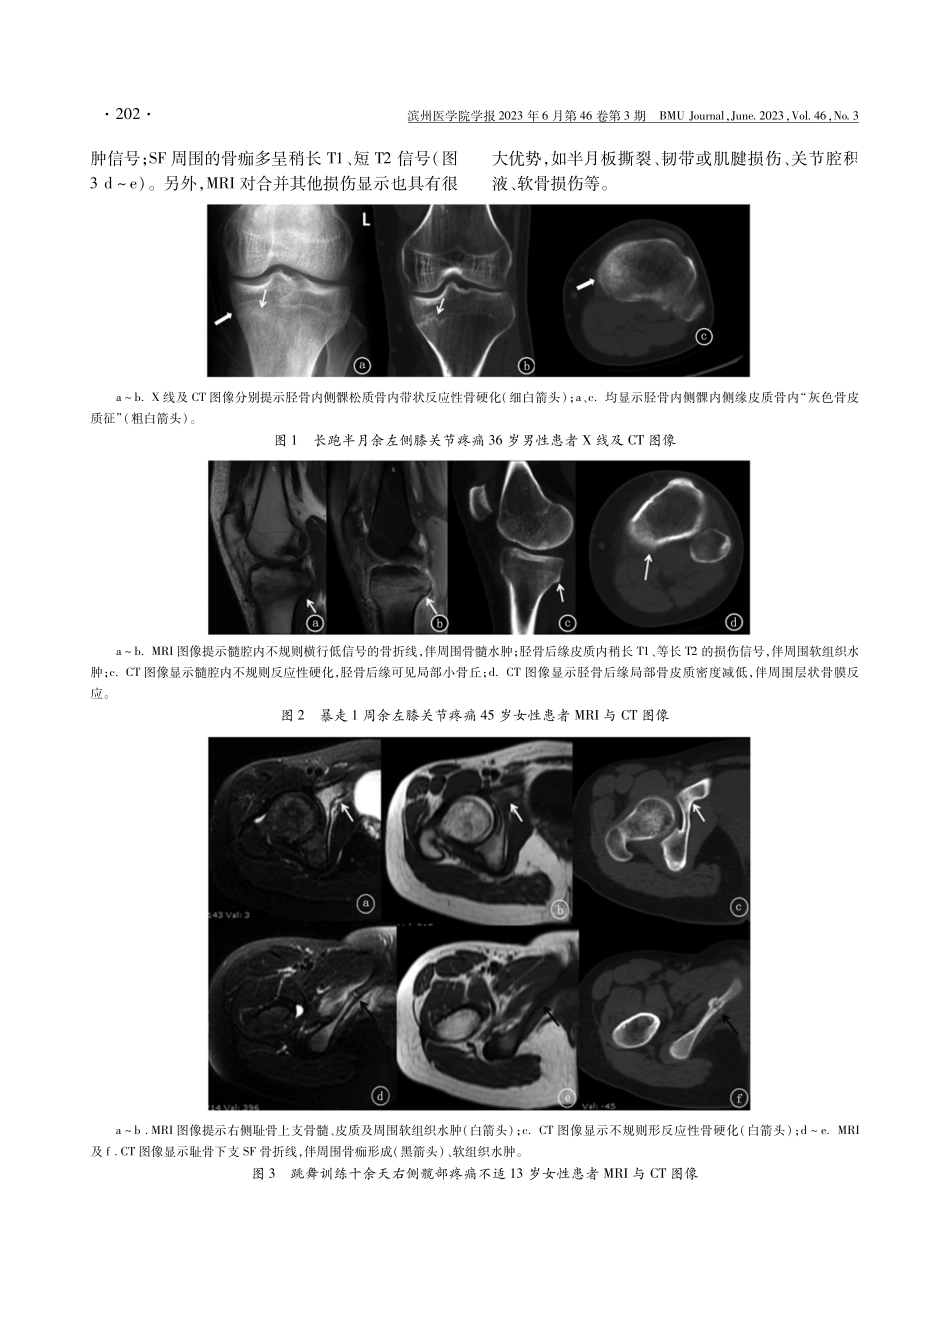

基金项目:漯医专创新创业发展能力提升工程团队项目(2019LYZTD012);漯医专科技创新项目(2022KJYB48)通信作者:周山,Email:zhoushanmri@163.com79例城镇居民应力性骨折的影像学特点孙英杰刘晓梅李光辉周山漯河医学高等专科学校第二附属医院影像科河南漯河462300【摘要】目的探讨城镇居民应力性骨折(SF)的影像学表现。方法对79例城镇居民SF患者的影像学资料进行分析。结果79例患者中共检出109处SF:其中长骨中胫骨近段是SF最常见的发病部位(61,56.0%);跟骨和耻骨则分别是四肢短骨及扁骨中SF最常见的发病部位[(9,8.3%)、(4,3.7%)]。磁共振成像(MRI)检出的SF影像图像中,骨膜/骨髓及软组织损伤、骨皮质损伤、骨折线的检出率较高(100%、78.1%、63.8%);CT检出的SF影像图像中,骨皮质损伤、反应性硬化、骨折线及骨痂检出率较明显(60%、50%、40%、40%);而在X线检出的SF图像中,反应性硬化、骨折线、骨痂及皮质损伤则相对明显(62.5%、37.5%、31.5%、31.5%)。结论城镇居民患者的SF具有特征性影像学表现,而MRI对于早期SF的诊断具有重要价值。【关键词】应力性骨折;X线;CT检查;磁共振成像【中图分类号】R445;R683【文献标志码】A【文章编号】10019510(2023)0302005DOI:10.19739/j.cnki.issn10019510.2023.03.010Retrospectiveanalysisofimagingfeaturesof79urbanresidentswithstressfracturesSUNYingjieLIUXiaomeiLIGuanghuiZHOUShanDepartmentofImaging,theSecondAffiliatedHospitalofLuoheMedicalCollege,Luohe462300,Henan,P.R.China【Abstract】ObjectiveToinvestigateimagingfindingsofstressfracture(SF)inurbanresidents.MethodsTheclinicalandimagingdataofpatientswithSFwerec...